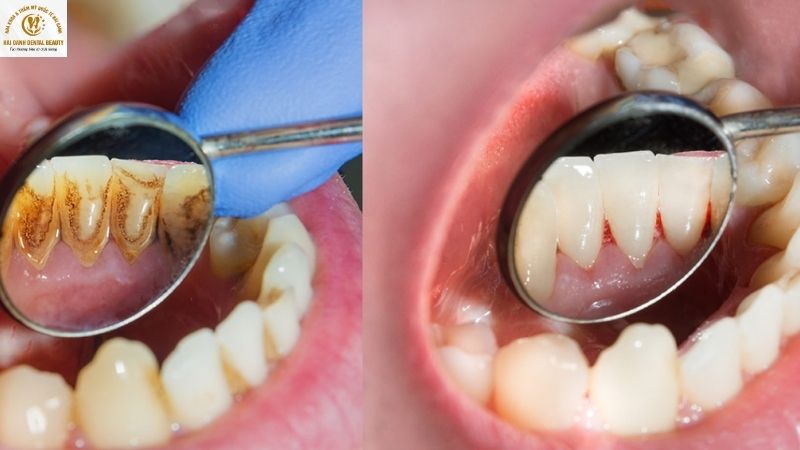

Cạo vôi răng là quá trình loại bỏ lớp cặn bẩn và vết ố bên ngoài này, giúp răng trở về màu sắc tự nhiên ban đầu của nó. Điều này tạo cảm giác răng trông sáng hơn, sạch hơn. Tuy nhiên, nó không làm thay đổi màu sắc bên trong của răng.

- Cao răng và mảng bám: Đây là những lớp cặn bẩn tích tụ từ thức ăn, nước bọt và vi khuẩn, thường có màu vàng, nâu hoặc đen. Chúng bám chặt trên bề mặt răng, gây ra các bệnh lý và che lấp màu sắc tự nhiên của men răng.

Lấy cao răng chỉ giúp làm sạch mảng bám chứ không làm trắng răng